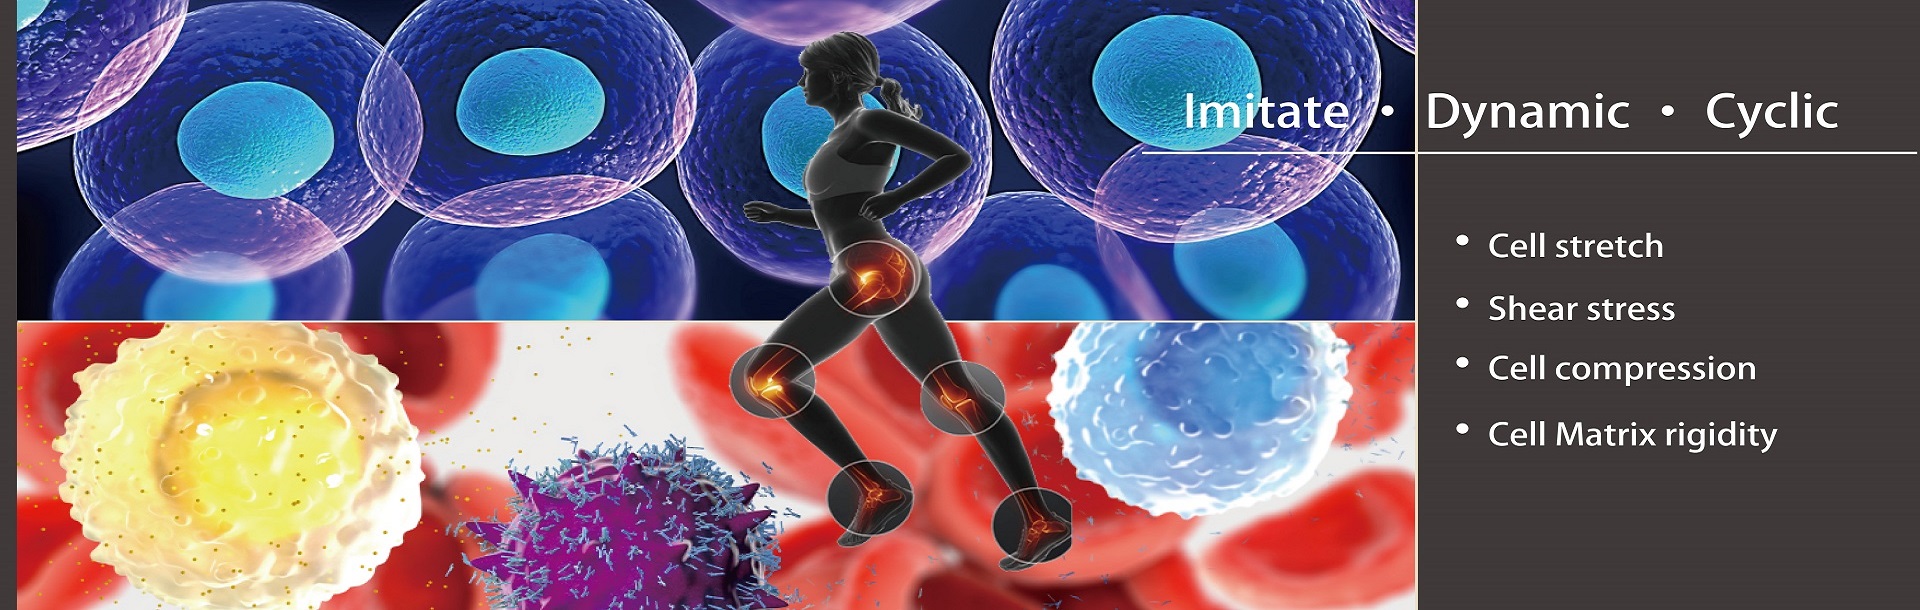

细胞~揭开富贵病背后的硬化真相

高盐、高脂、久坐、熬夜……现代生活方式在悄悄改变我们的身体。越来越多的人年纪轻轻就背上了“富贵病”标签——高血压、动脉粥样硬化、代谢综合症,这些表面看似无害的慢性病,其实正在深层次地侵蚀我们的心血管系统。

细胞~ 24小时预测改善退化性关节炎关节炎模型

膝关节健康关键在于软骨细胞的正常结构。健康的软骨细胞多为圆形或椭圆形,规则地分布于由胶原与聚糖组成的基质网络中,协同维持关节的运动功能。而在退化性关节炎(OA)中,软骨细胞出现形态异常、数量减少,基质代谢失衡,导致软骨功能逐步丧失。